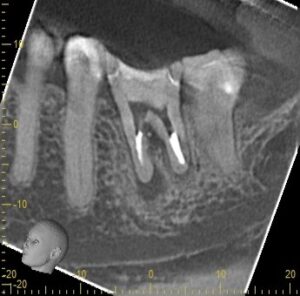

診断の正確さ:パーフォレーションの位置と大きさを特定する

東京(江戸川区小岩)の根管治療専門外来|笠原デンタルオフィスで、パーフォレーション(穿孔)」は根管治療の失敗!?原因と症状、対処法について解説

修復の第一歩は、穴の正確な情報を把握することです。

肉眼や通常のレントゲンだけでは、根管の影に隠れて穴の位置を正確に特定することはできません。

歯科用CBCT(3次元レントゲン)

通常のレントゲンでは判別できない、穿孔部位と周囲の骨との位置関係、感染の広がりを立体的に解析します。

これにより、修復材を詰める深さや方向を正確に計画できます。